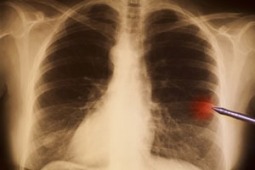

Afatinib i erlotynib w leczeniu zaawansowanego raka płuca - wyniki badania LUX-Lung 8

Płuco i opłucna